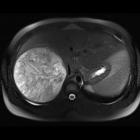

• Hepatic hemangioma - Ganzer Fall bei Radiopaedia